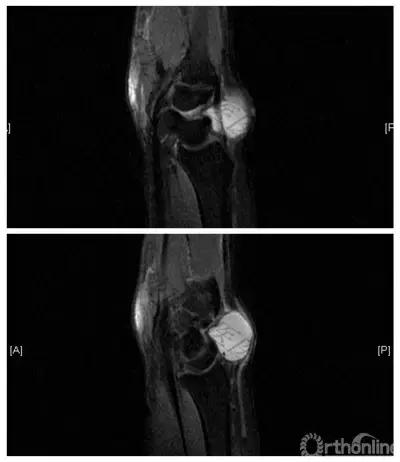

△月骨无菌性坏死并TFCC损伤(左图:MRI示月骨信号改变,中图:镜下发现月骨变性坏死,右图:术后X线)